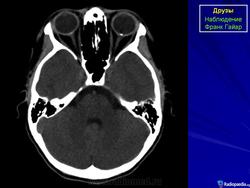

При КТ-исследовании изредка попадаются больные с наличием у них в области диска зрительного нерва плотных включений, которые могут быть приняты за инородные тела. Это так называемые друзы. Друзы диска зрительного нерва – довольно редкое заболевание, характеризующееся гроздевидными округлыми возвышениями над диском нерва, состоящими из гиалина. Иногда в них откладывается известь. Считают, что друзы имеют наследственный характер.

КТ-семиотика

При КТ друзы отличаются локализацией – только в диске зрительного нерва, небольших размеров (не более одного миллиметра) и правильной округлой формы. Друзы совершенно однородны, не дают артефактов и имеют определенную плотность (150-200 НU).